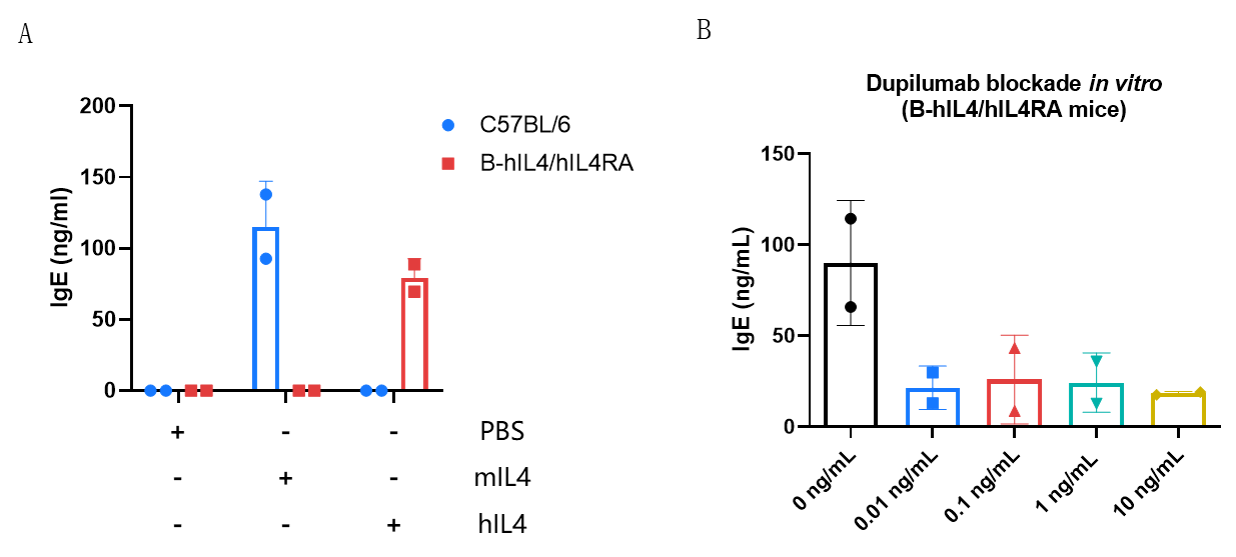

IgE production in B-hIL4/hIL4RA mice and its inhibition by dupilumab (in house). (A) Splenic B cells from C57BL/6 and B-hIL4/hIL4RA mice were cultured with LPS alone or together with 50 ng/mL mIL-4/hIL-4. Culture supplements were harvested on day 6 for IgE quantification by ELISA. (B) Splenic B cells from B-hIL4/hIL4RA mice were incubated with increasing doses of dupilumab (in house) for 30 min before adding LPS and hIL-4 (50 ng/mL). Supernatant was harvested on day 6 for IgE quantification by ELISA. B cells from B-hIL4/hIL4RA mice produced IgE similarly to C57BL/6 mice in response to species-specific IL-4, while dupilumab effectively blocked IgE production.